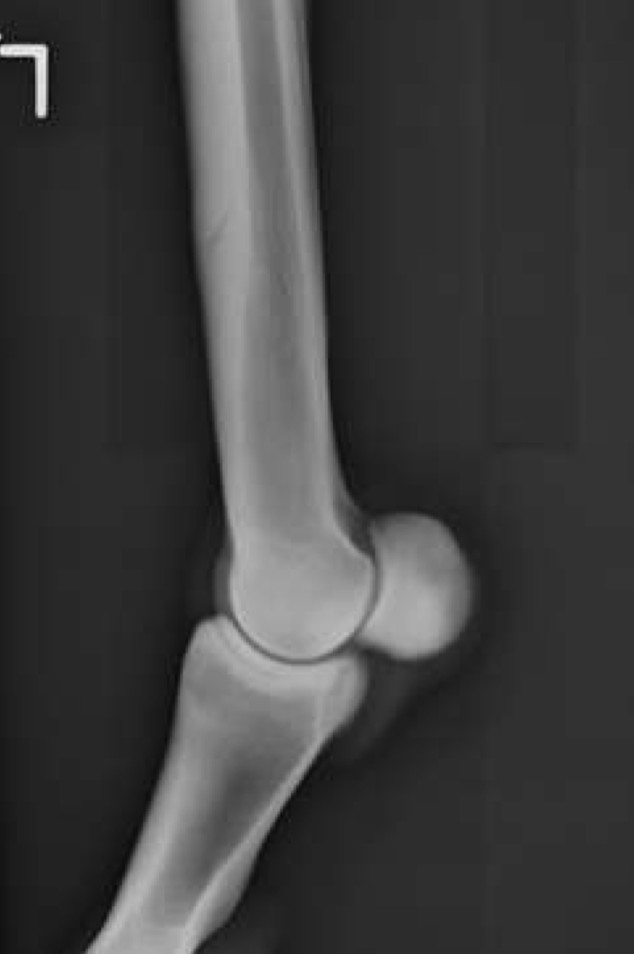

This horse has an incomplete fracture of P1. What is the recommended treatment?

Lag screw or cast only + strict stall rest

When drilling for P1 fractures, the most proximal screw must be within ____ of the sagittal groove

5 mm